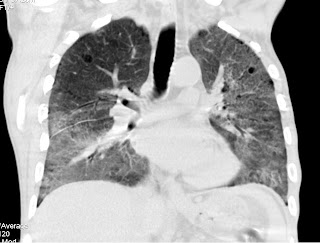

Mujer de 45 años en estudio por dolor epigástrico de 3 meses de evolución

Presentanos los protocolos de actuación ante este tipo de imagen

Enséñanos algunas imágenes /ejemplos con las diferentes técnicas a emplear